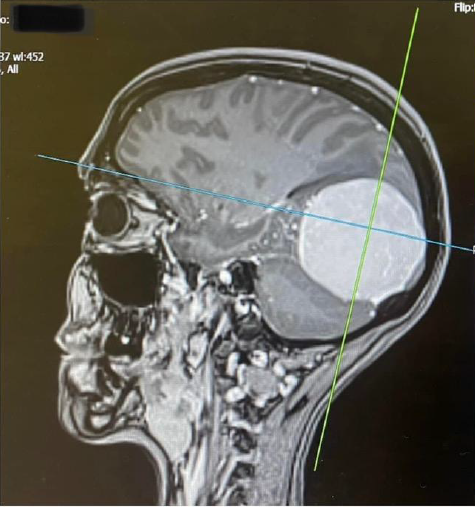

someone with me. I knew instantly that it didn’t sound good but tried to stay positive. The next day the neurologist told me that the scan showed that I had a large Meningioma in my occipital lobe, these tumours are usually benign and slow growing, but as mine was already quite big I would need surgery to remove it as there really was no other option. What a shock! I don’t know what I expected to hear but it wasn’t that. I was told the surgery would probably be within weeks, it was a lot to take in. I had bloods done there and then in preparation and cried all the way home.

I had an appointment with the neurosurgeon at UHCW on 14th April, he showed me the MRI scan and I was shocked at how big the tumour was (5.9cm), we discussed the surgery and the risks and he basically told me it had to come out and he would prefer it to be sooner rather than later so he added me to the list and I just had to wait for a date.